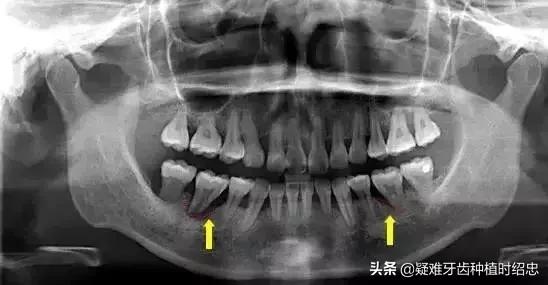

1、牙周袋形成:由于炎症的扩展,牙周膜被破坏,牙槽骨逐渐吸收,牙龈与牙根分离,使龈沟加深而形成牙周袋。可用探针测牙周袋深度。

3、牙齿松动:由于牙周组织被破坏,特别是牙槽骨吸收加重时,支持牙齿力量不足,出现牙齿松动、移位等现象。此时患者常感咬合无力、钝痛,牙龈出血和口臭加重。